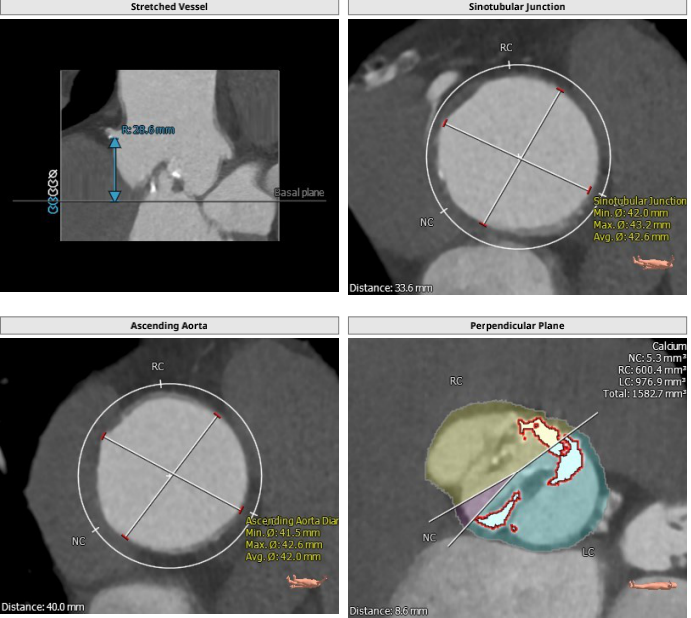

主动脉根部解剖: